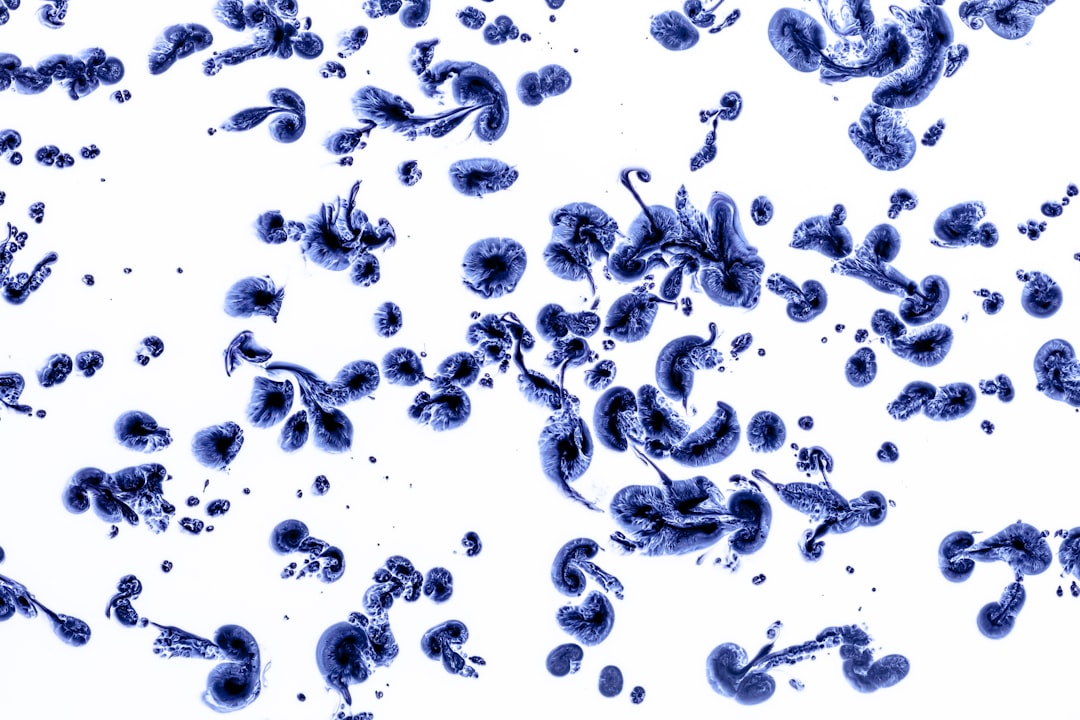

결핵은 폐를 주로 공격하지만, 몸의 다른 부위에도 영향을 줄 수 있습니다. 이 병은 전염성이 강해, 특히 밀접한 환경에서 감염될 가능성이 높습니다. 그래서 보건소에서 제공하는 무료 결핵검사 및 치료 방법은 매우 중요합니다. 검사는 간단하고 빠르며, 일반적으로 X-ray 또는 가래 검사로 이루어집니다. 이런 검사를 통해 조기 발견이 가능해지니, 정기적으로 검사를 받는 것이 좋습니다.

결핵 검사 결과 양성으로 나왔다면, 즉시 치료를 시작해야 합니다. 보건소에서 제공하는 무료 결핵검사 및 치료 방법 중 가장 핵심적인 부분은 바로 약물 치료입니다. 결핵 치료에는 일반적으로 6개월에서 9개월가량 치료약을 복용해야 하며, 매우 효과적입니다. 중요한 것은 치료를 중단하지 않고, 정해진 기간 동안 복용하는 것입니다.